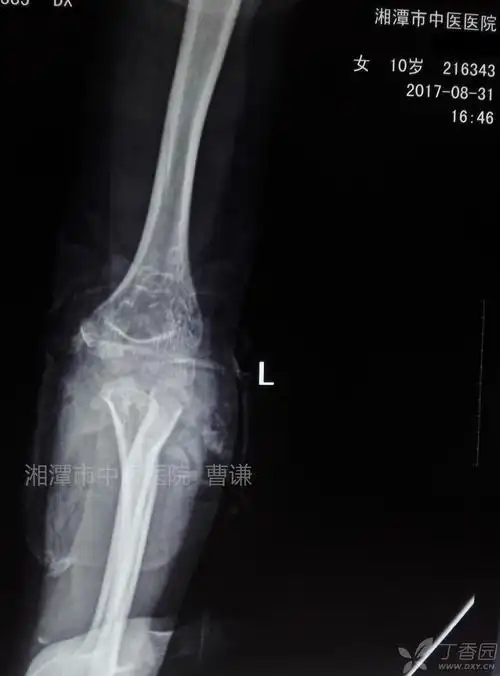

桡骨颈骨折合并鹰嘴骨折的保守治疗 [病例帖]

活动受限,在外院行拍片及ct检查后就诊于我院 临床诊断:左桡骨颈骨折